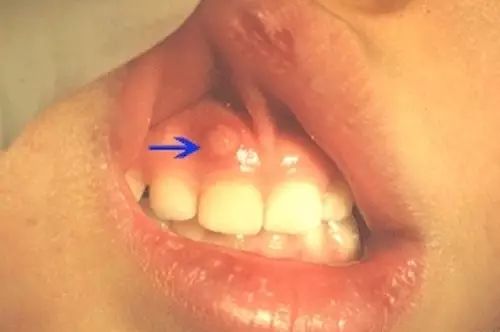

为了方便理解,已经给你配好了图。

并不会!牙龈脓包是个狡猾的家伙,它可能在蛀牙的牙龈位置表现出来,像这样的:

但也有可能脓包位置所相对应的牙齿,没有蛀牙。就如给我们私信的家长所误认为的,“牙齿好好的呀,为什么会起脓包呢”。

第一种可能是,相对应位置的牙齿蛀牙或牙齿受过外伤,但不仔细观察,无法分辨,所以就觉得它像正常牙一样存在着。

第二种可能是,被蛀坏的是另有其“牙”,只是脓液跑到别的牙齿所在的牙龈位置释放出来。